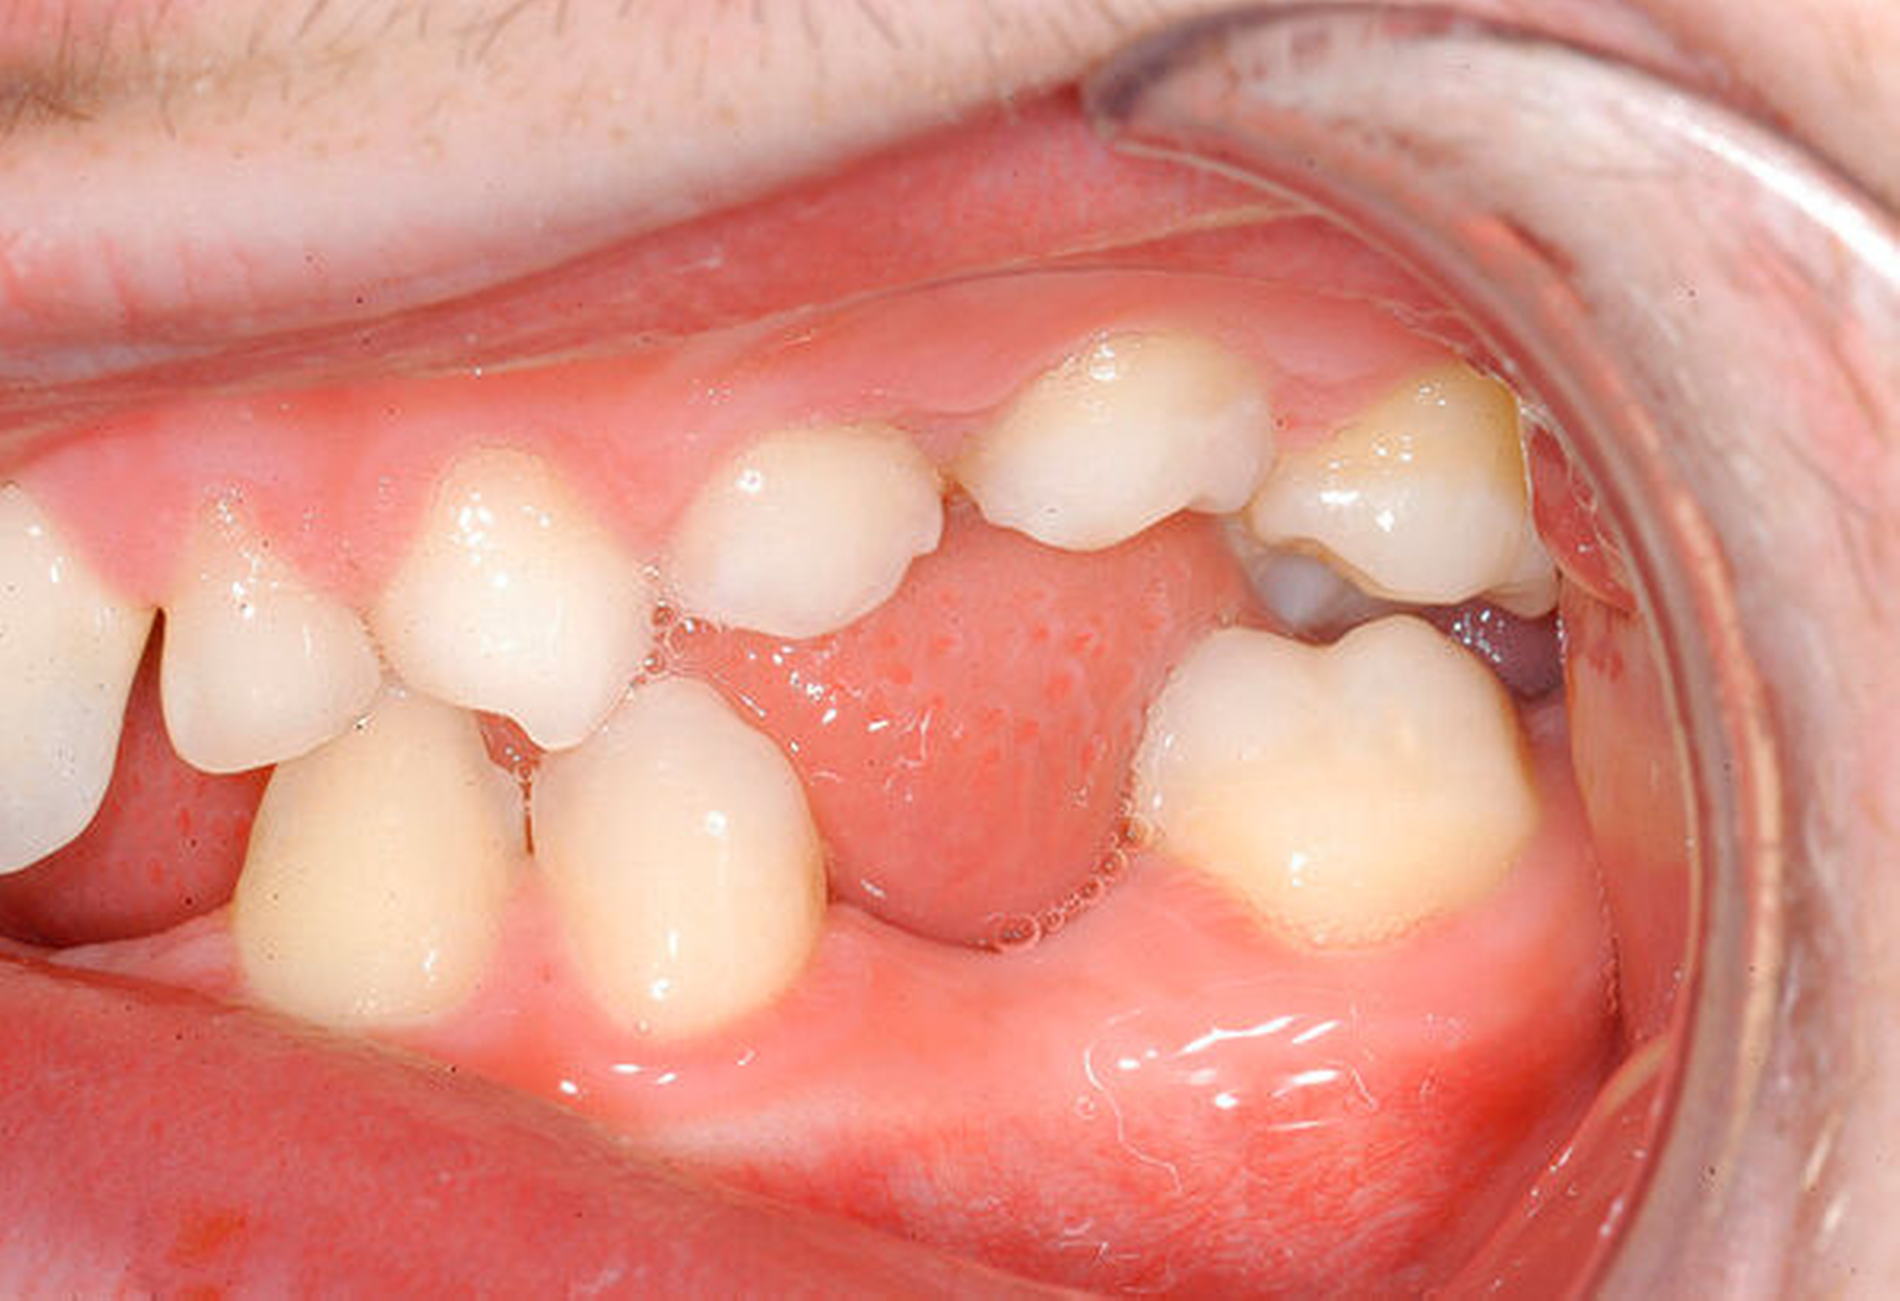

Beim intraoralen Befund imponierten neben multiplen Lücken ein partiell seitlich-offener Biss, eine auffällig konische Form der oberen mittleren Schneidezähne sowie persistierende Milchzähne (Abbildungen 2 bis 4). Zusammen mit der angefertigten Panoramaschichtaufnahme (Abbildung 5) konnte der Verdacht einer ausgeprägten Oligodontie bestätigt werden – insgesamt waren 22 Zähne inklusive der Weisheitszähne nicht angelegt. Auf Grundlage der bestehenden Befunde wurde der Verdacht einer genetischen Ursache der Symptome geäußert und dem Patienten zunächst eine molekulargenetische Abklärung mit der Verdachtsdiagnose „genetisch bedingte Zahnnichtanlagen / ektodermale Dysplasie“ empfohlen. Bei der Sequenzanalyse wurde eine Mutation im WNT10A-Gen nachgewiesen und somit die klinische Verdachtsdiagnose bestätigt.